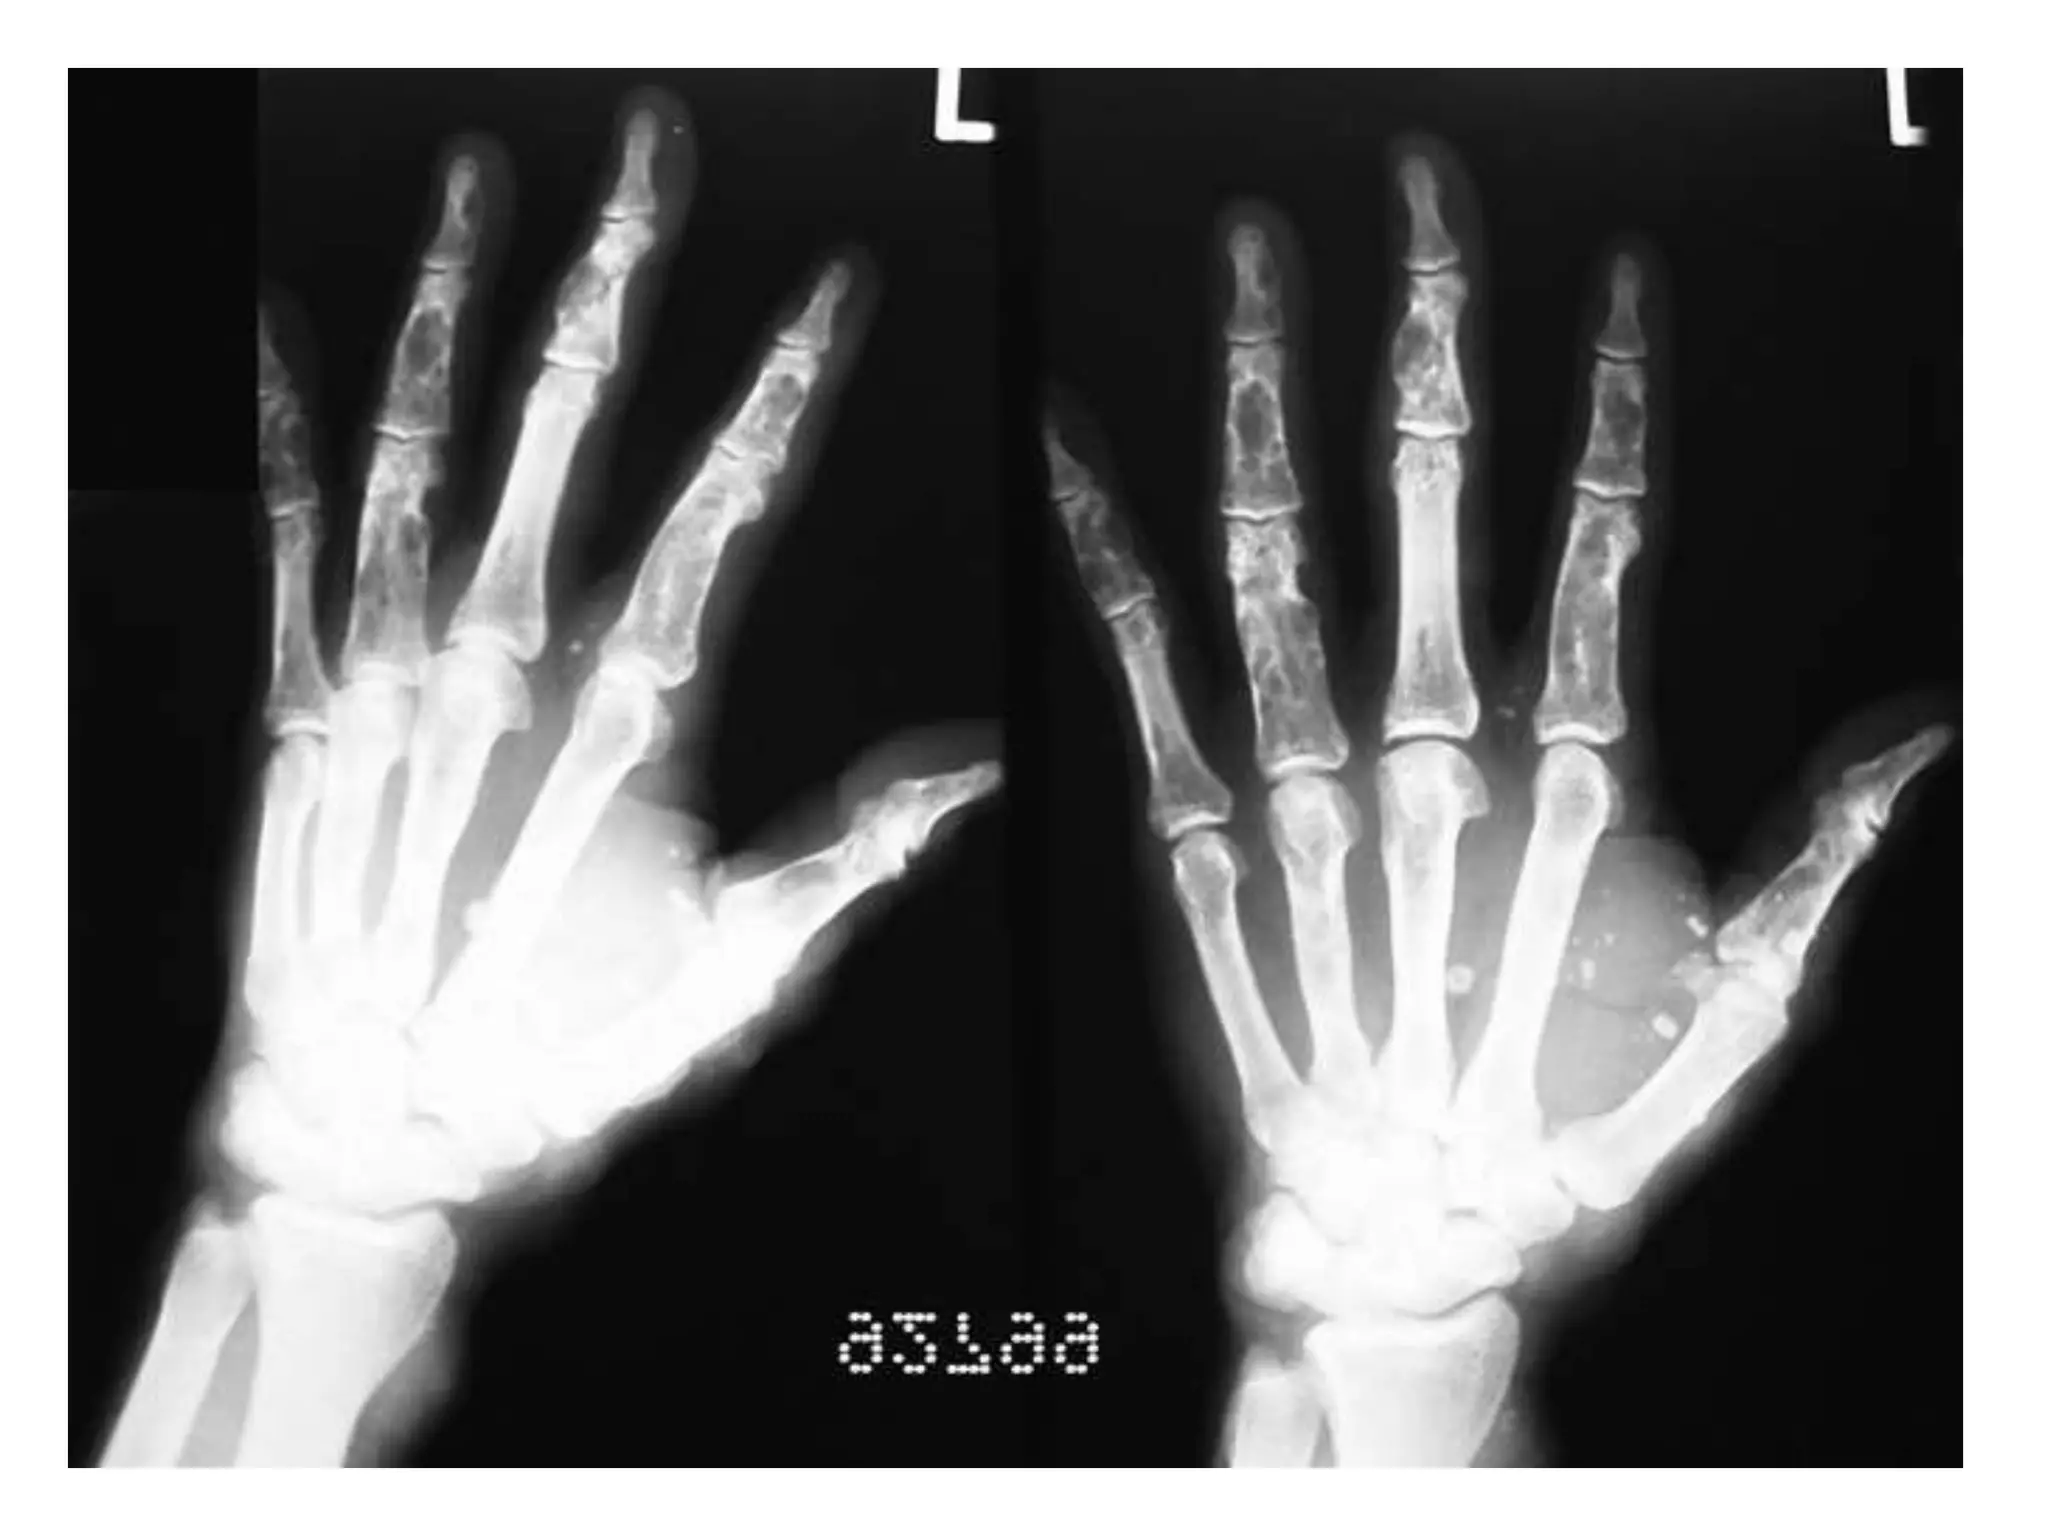

MARFAN’S SYNDROME

Due to cross linkage defect in collagen and elastin

(genetic mapping is fibrillin gene on chromosome 15)

c/f :

Tall with long legs and arms

Chest pectus excavatum(flat/hollowing)

Digits long(spider fingers- arachnodactyly)

Spine spondylolisthesis, scoliosis

Flatfeet

Associated: high arched palate, hernia, lens dislocation, retinal

detachment, aortic aneurysm, mitral/aortic incompetence, joint laxity